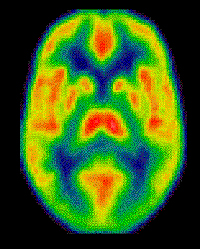

Tomografia de positrones